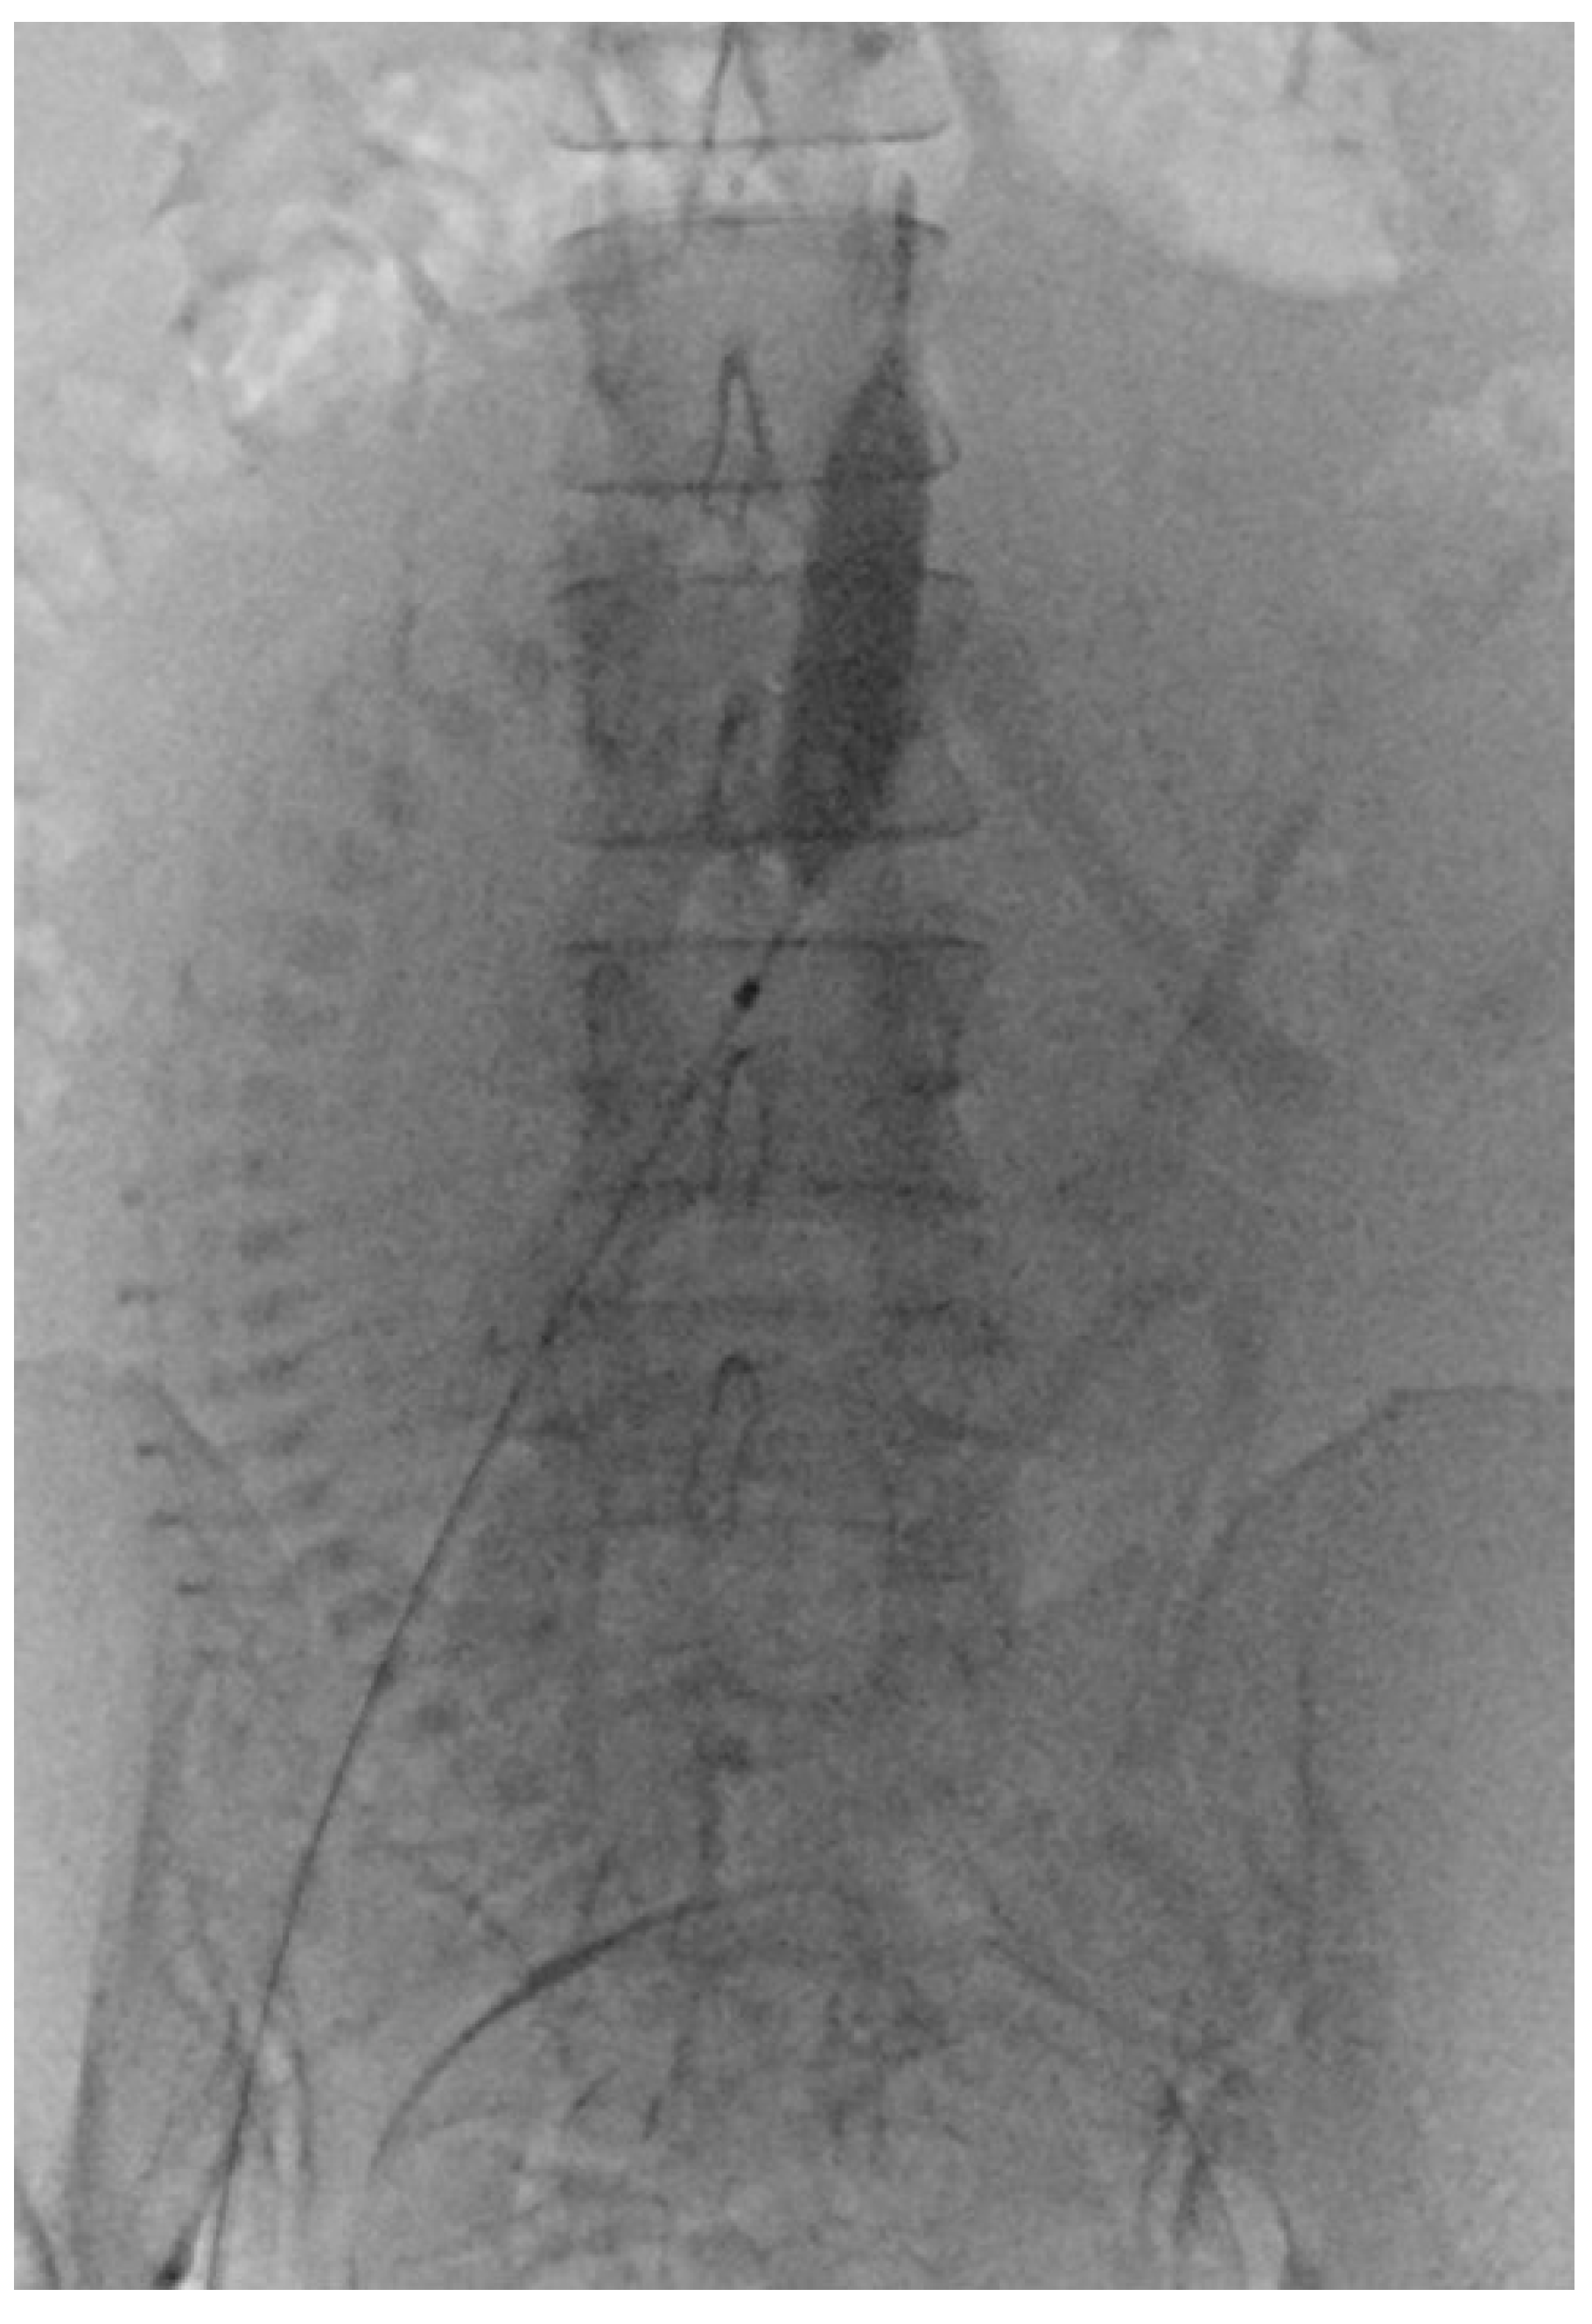

2.6. PABO Procedure

Before PABO, the patients were fully informed of the risks and complications. The procedure involved femoral artery puncture, sheath insertion, and placement of a 7 Fr occlusion balloon catheter. After successfully positioning the catheter, it was securely fastened to the skin. Subsequently, patients were moved from the interventional catheter room to the operating room for a CS. The CS procedure was performed under spinal anesthesia immediately following balloon placement. Following delivery and umbilical cord clamping, the occlusion balloons were inflated in accordance with the obstetrician’s instructions (Figure 2). After delivery, the balloons were deflated prior to skin closure. The radiologist removed the catheters once the patient’s vital signs stabilized, and compression was applied to the puncture sites.

Figure 2. Prophylactic aortic balloon occlusion during a cesarean section for placenta accreta spectrum and placenta previa.